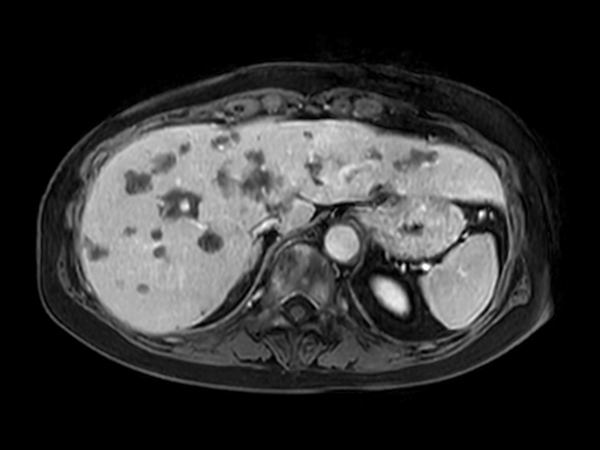

Axial T2w SSh